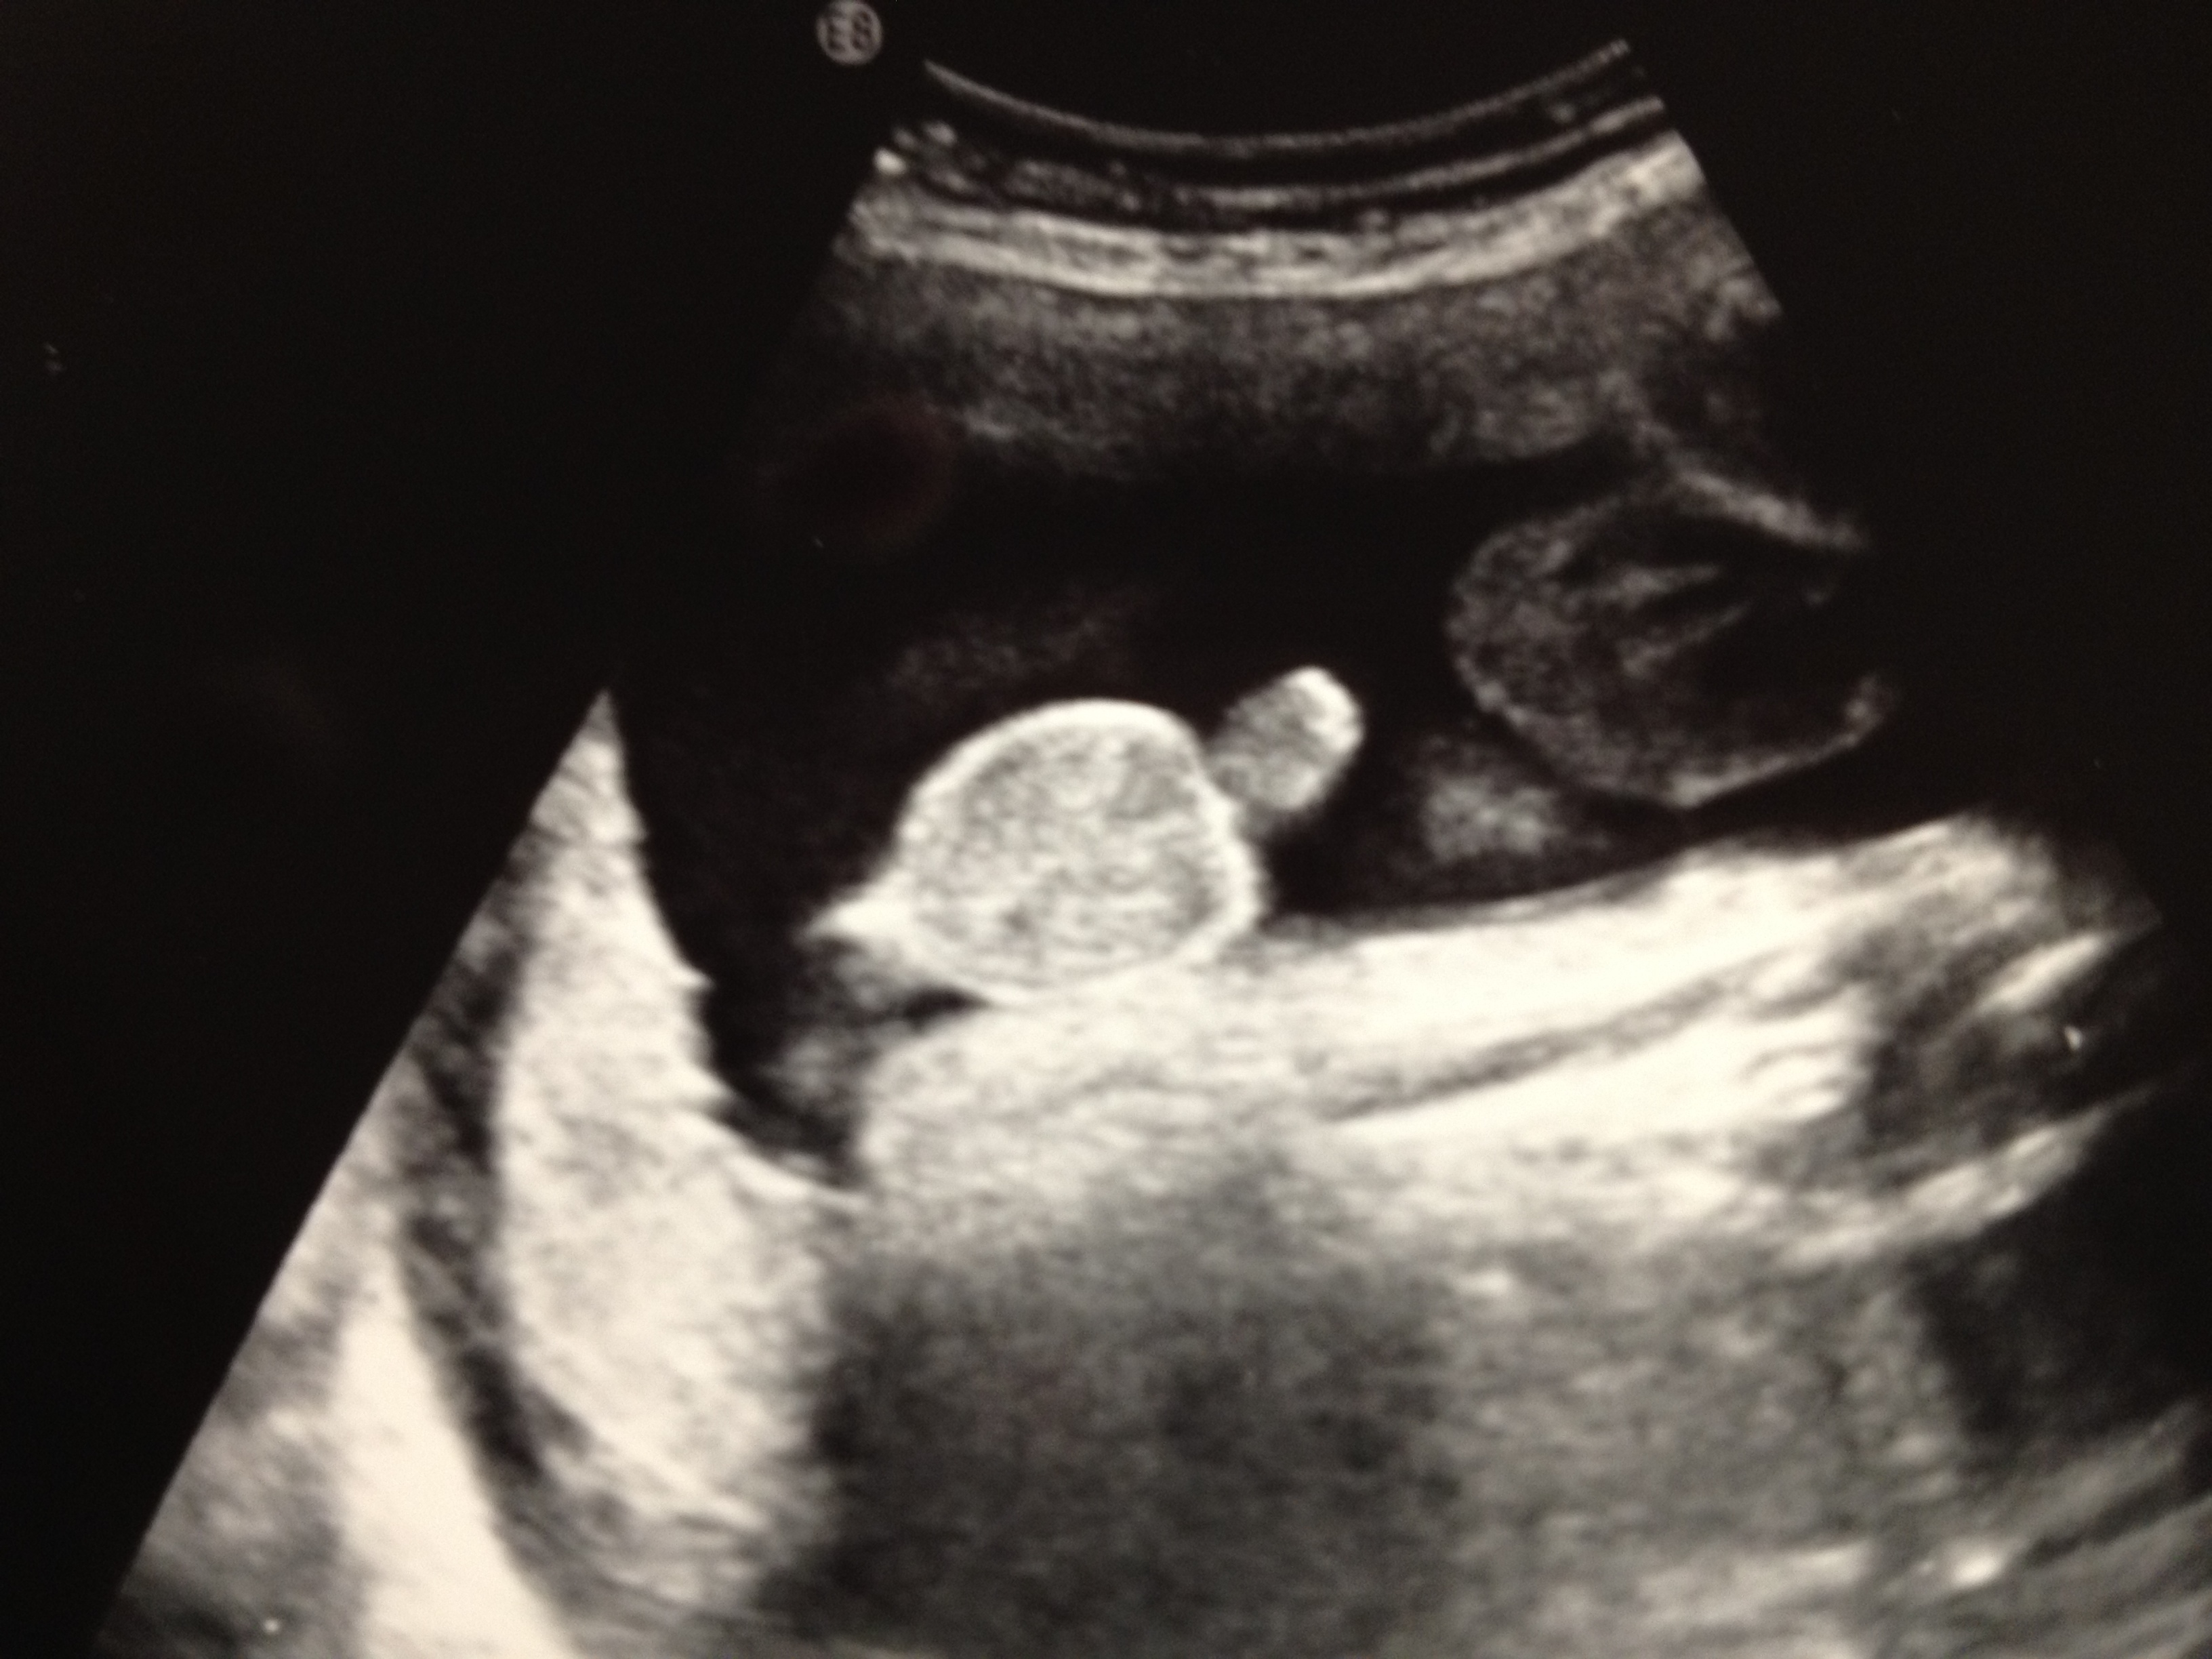

Baby Update- Well Mr. Man, we went to the Dr yesterday, and you are measuring 3lbs 10 oz. That puts you in the 43% percentile and the Dr said that was great and you are one day ahead of your due date. My placenta has moved up out of the way, so I don’t have to have a mandatory c-section. Yay! You were in the head down position and your feet were up by your head, so you were completely folded in half with your butt in my ribs! We got to see you wave your little finger around at us, and it was so cute! They also did a 3D pic of your face, and you definitely have fatter cheeks than the last time we got to see you! Since we are so close to the end (under 9 weeks!) I now start going to our appointments every 2 weeks so the Drs can keep an eye on everything. You’ve been having hiccups that make you really mad so you start squirming around all over the place. According to the baby books, you are about 16 inches long (they don’t actually measure you at the Dr’s office anymore because you are so big and squished up) and about the size of a pineapple. All 5 of your senses are in working order, although your nose won’t pick up anything until after you’re born since smell is transferred through air.

Here are the 3 ultrasound photos from the appointment including one of your boy parts! (Sorry, I know this will be soooo embarrassing when you’re older!)